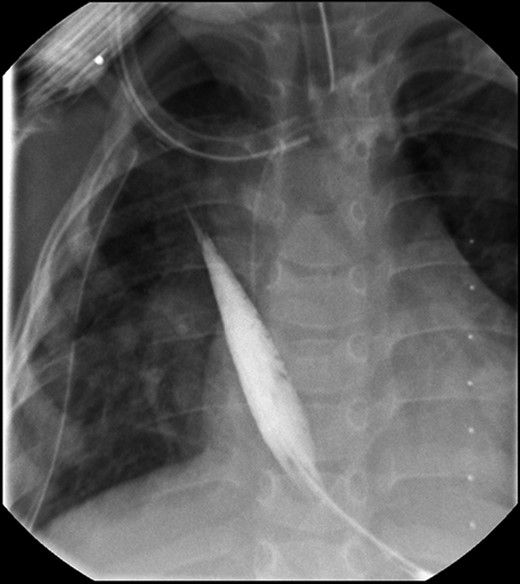

Daily tightening of her traction sutures was performed until the distal esophageal segment reached the chest wall (Fig. 2). The cervical esophagostomy was also sequentially lengthened and eventually internalized. Three traction suture revisions and two proximal esophageal lengthening operations were performed before esophageal continuity was re-established (46 days). Two subsequent anastomotic leaks occurred; 1 anastomotic leak was repaired surgically, whereas one subsequent leak was managed nonoperatively with a chest tube. Five dilations and, one, 13-day retrievable stent placement were needed for anastomotic narrowing. A comparative postoperative esophagram and intraoperative esophagram illustrated neither a stricture nor an anastomotic leak (Fig. 3). Total hospitalization was 112 days.

An intraoperative esophagram following a routine esophagogastroduodenoscopy (EGD) is pictured on the right, as compared with her postoperative esophagram on the left. The EGD was performed on this patient following her anastomosis (Foker Stage II); the native esophagus was now in continuity. Contrast was injected above the level of the anastomosis, which demonstrated neither leak nor stricture.